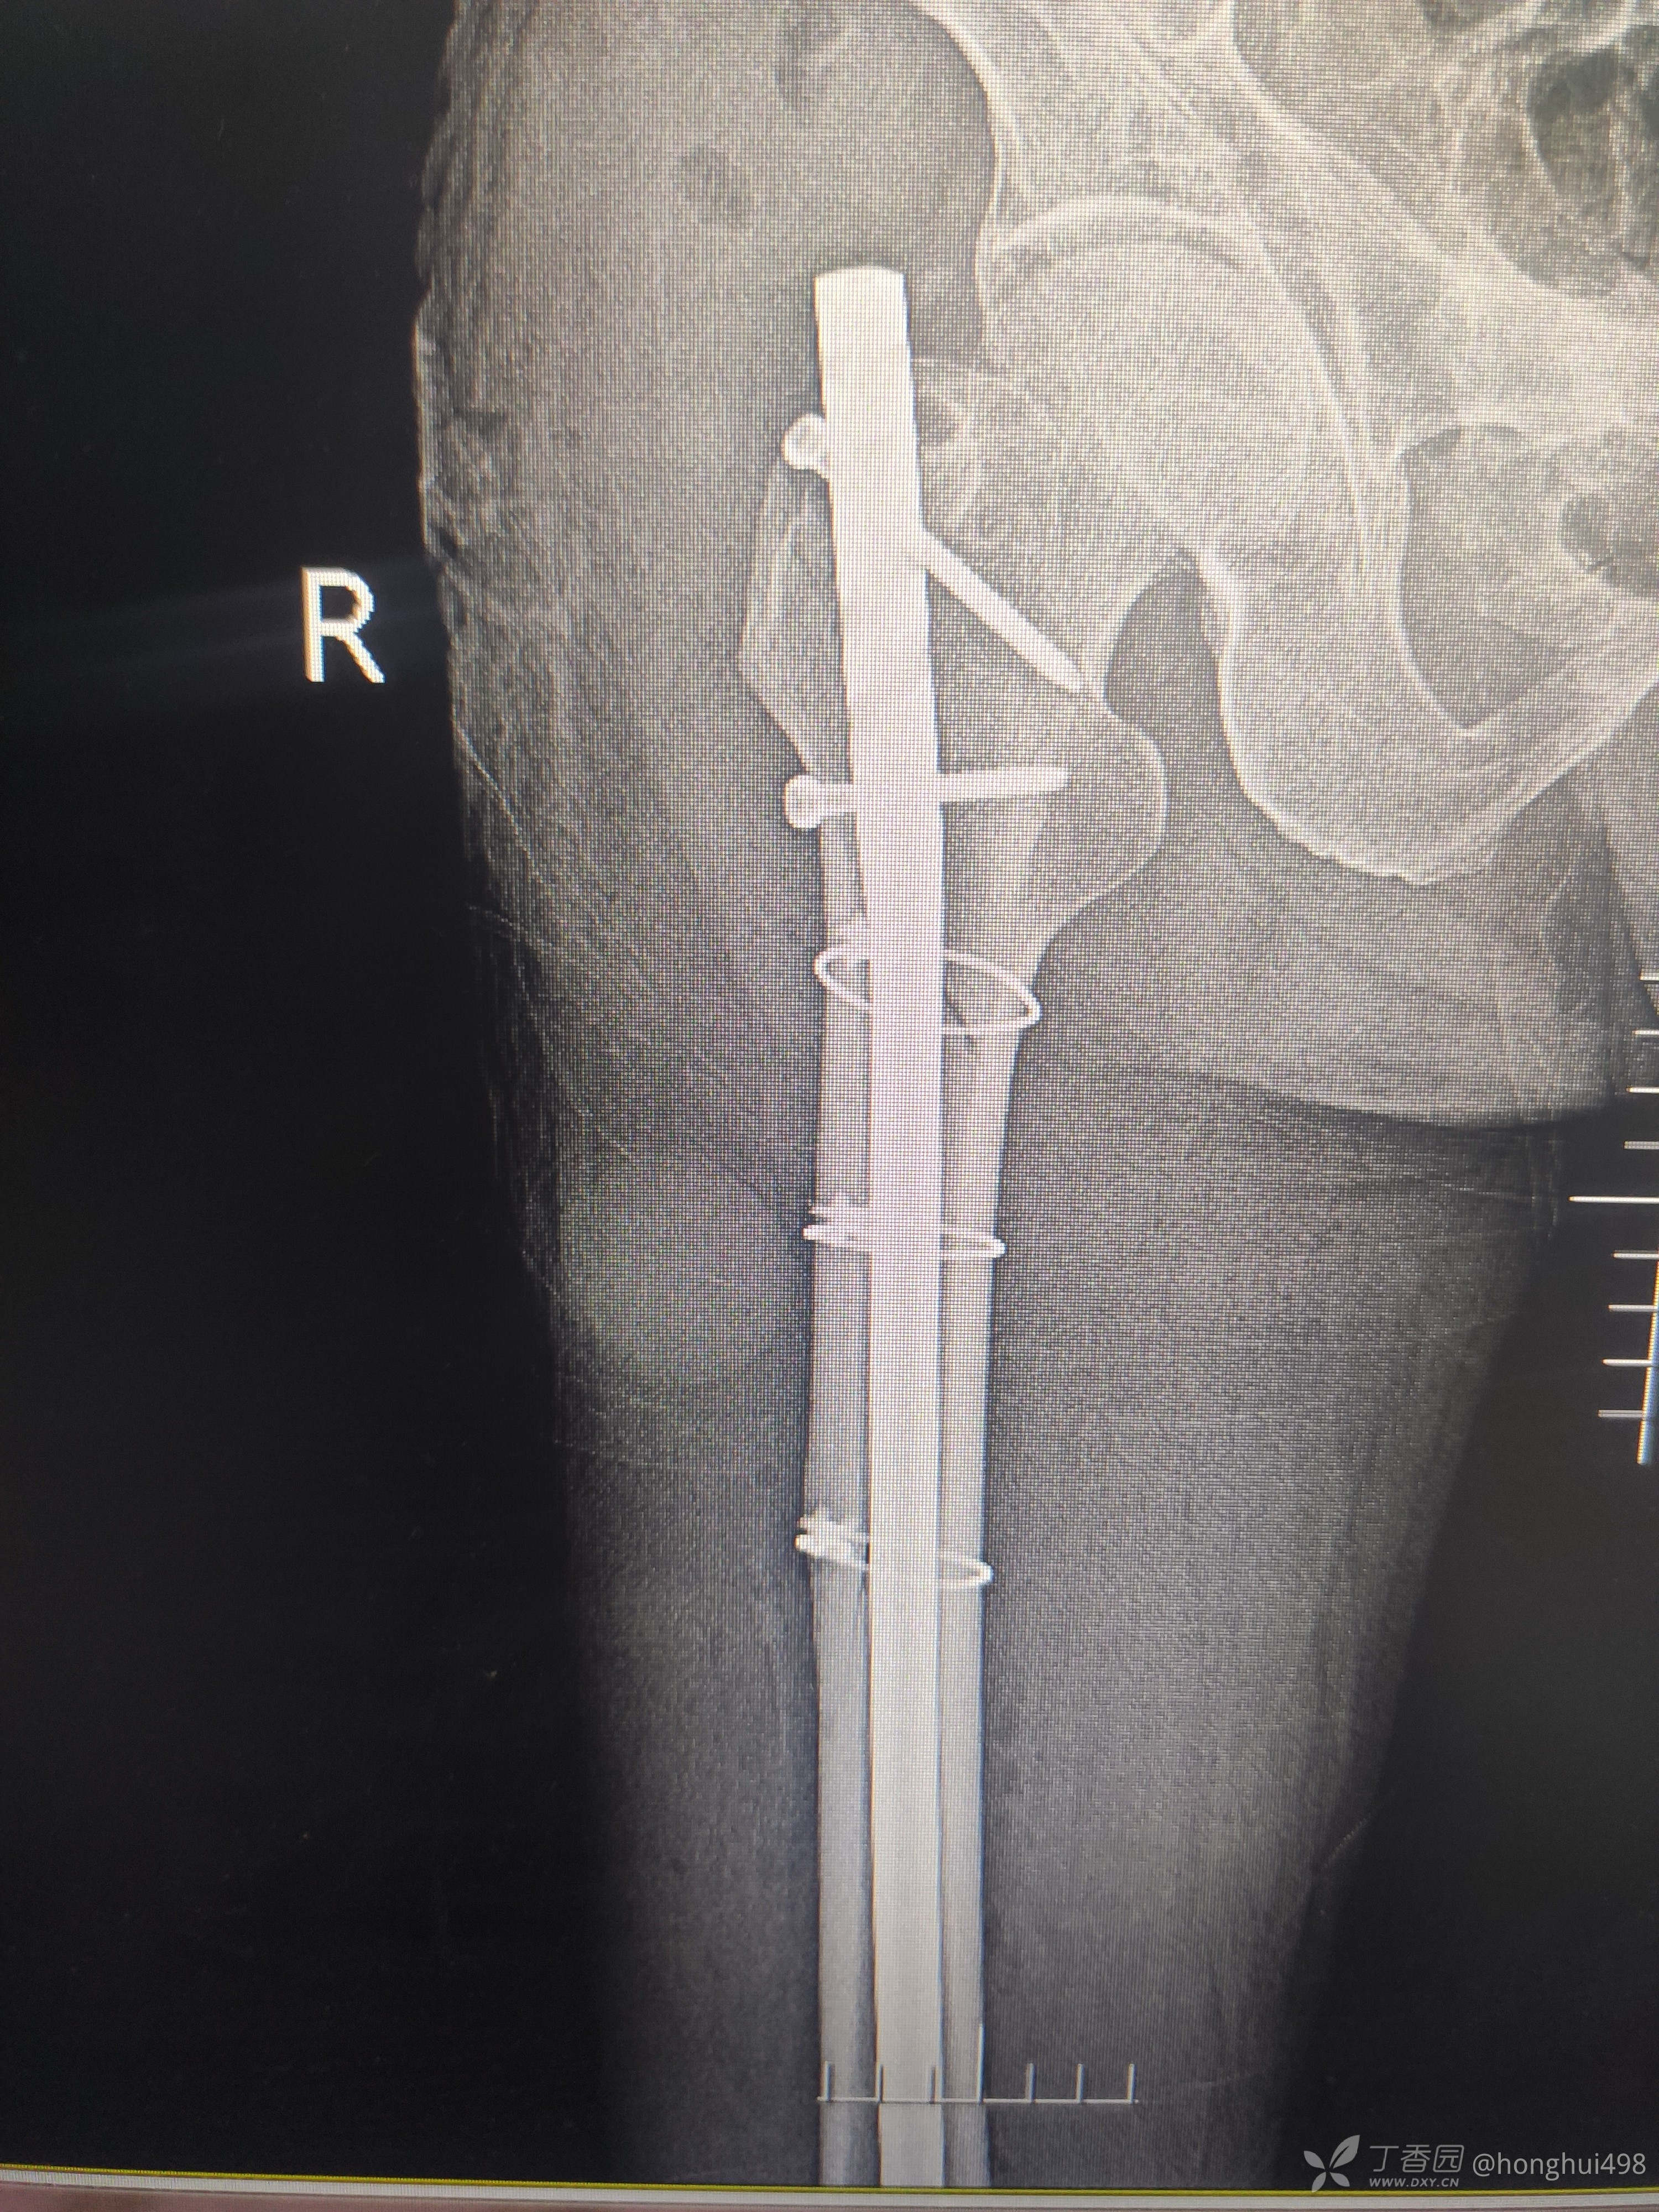

男性57岁,骑电动车摔伤致右大腿疼痛,畸形,活动障碍。

入院诊断:右股骨近端骨折,右股骨大粗隆骨折。

腰麻硬膜外联合麻醉下行骨折切开复位髓内钉+钢缆固定。